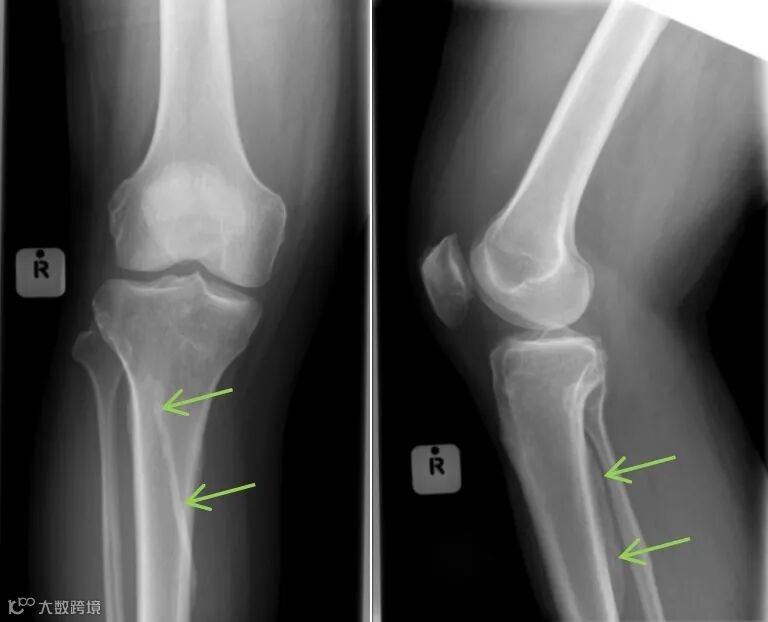

图3 右侧比目鱼肌线